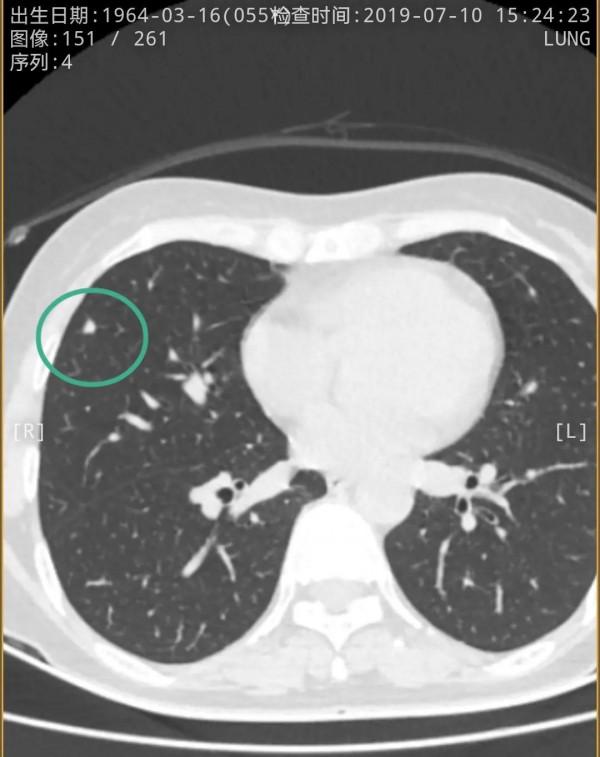

我們先來看2021年12月的,右肺多發實性結節,邊緣相對平直,膨脹性不明顯,紅色圈起來的主病灶周邊一圈密度高,中間密度低,還有點狀高密度,考慮肉芽腫性炎伴壞死(區域性纖維鈣化),次病灶藍色圈起來的形態也是類似的,骨窗看也是中間密度低,而周邊一圈密度高。那麼再來看2019年時是如何的呢?假如是惡性,應該有進展。但我們閱片後發現並沒有大的變化,由於掃描條件不同,中間密度低在平掃上不明顯,紫紅圈起來的和綠色圈起來的分別對應主病灶和次病灶。但當時有區域性靶掃描,結果形態與2年後的沒什麼區別,當時也已經是周邊一圈密度高,而中間密度低且均勻。所以此兩灶可基本認定為肉芽腫性炎伴壞死,可安全隨訪。最好半年查一次(因為正常沒結節也一年查一次呢)。